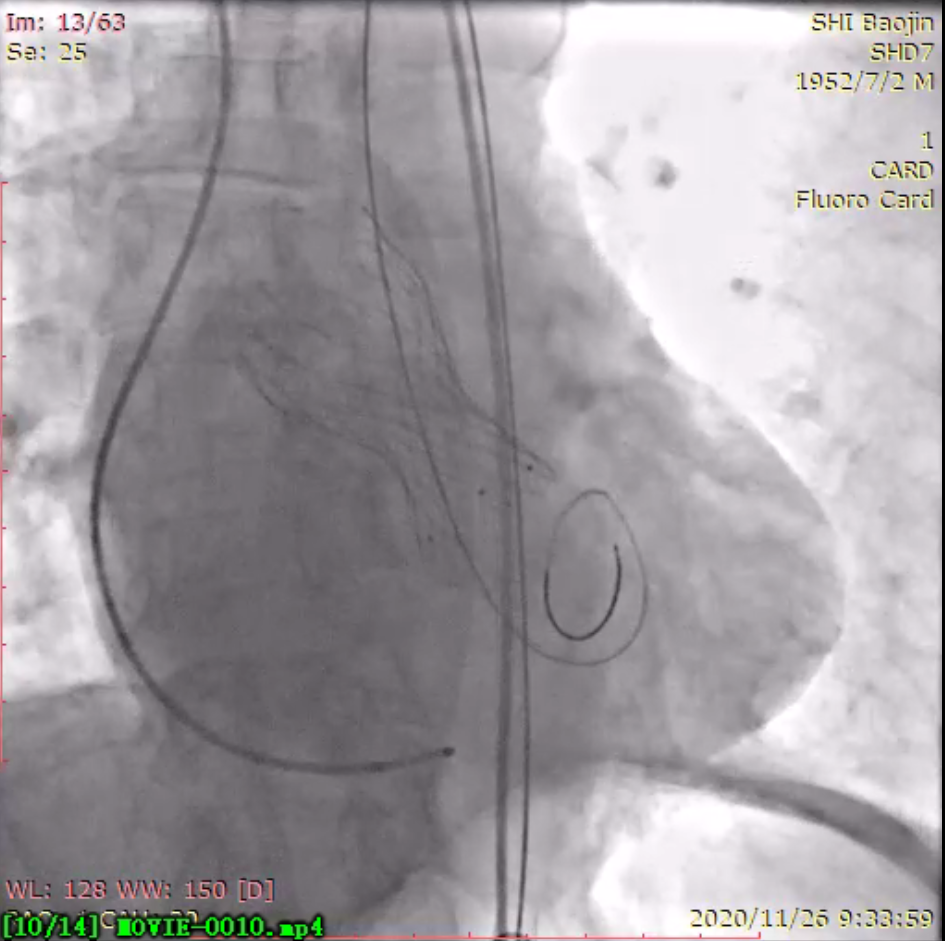

瓣膜释放后

同济大学附属同济医院党委书记许树长、院长程黎明到心脏导管室进行了关心慰问。术中患者主动脉跨瓣压差 67 mmHg,根据术前 CT 评估瓣环直径和术中球囊预扩张情况,选择合适的人工瓣膜,一次精准定位释放,复查跨瓣压差消失,实时食道超声心动图见轻微瓣周漏,效果良好,整个手术一气呵成。